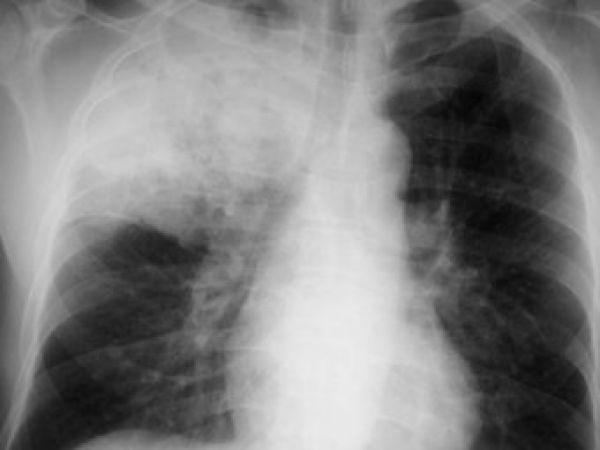

Больной жалуется на одышку. Кожные покровы его бледны; со стороны видимых слизистых может отмечаться синюшность. При аускультации (прослушивании) легких шум дыхания либо ослаблен, либо отсутствует. За счет уменьшения объема легкого при большом ателектазе может быть смещено в сторону поражения средостение; также на стороне поражения может быть высокое стояние диафрагмы. Диагноз подтверждается рентгенологически. Поскольку в закрытом пространстве альвеол присутствуют и развиваются микробы, ателектаз часто осложняется пневмонией.

На рентгеновских снимках выявляют следующие признаки, указывающие на спадение легочной ткани:

Однородное затемнение в области поражения. Размеры тени зависят от вида ателектаза: при долевом выявляется обширное затемнение, при сегментарном — в виде клина или треугольника, расположенного вершиной к корню легкого, дольковые ателектазы множественные и похожи на очаговую пневмонию. Дистензионный ателектаз расположен низко, около диафрагмы, имеет небольшие размеры и вид поперечных полос или темных дисков. Смещение органов: при компрессионном ателектазе смещение наблюдается в здоровую сторону, так как на стороне поражения давление больше, при обтурационном, наоборот – смещение будет в сторону ателектаза, так как на стороне поражения нарастает притягивающее отрицательное давление. Подъем купола диафрагмы – это видно по расположению печени.

Опытный врач заподозрит спадание легких на основе осмотра: грудная клетка больного будет ассиметричной при дыхательных движениях – за счет того, что ее пораженная половина не двигается, потому как легкое фактически не дышит (образно говоря, ему нечем дышать).